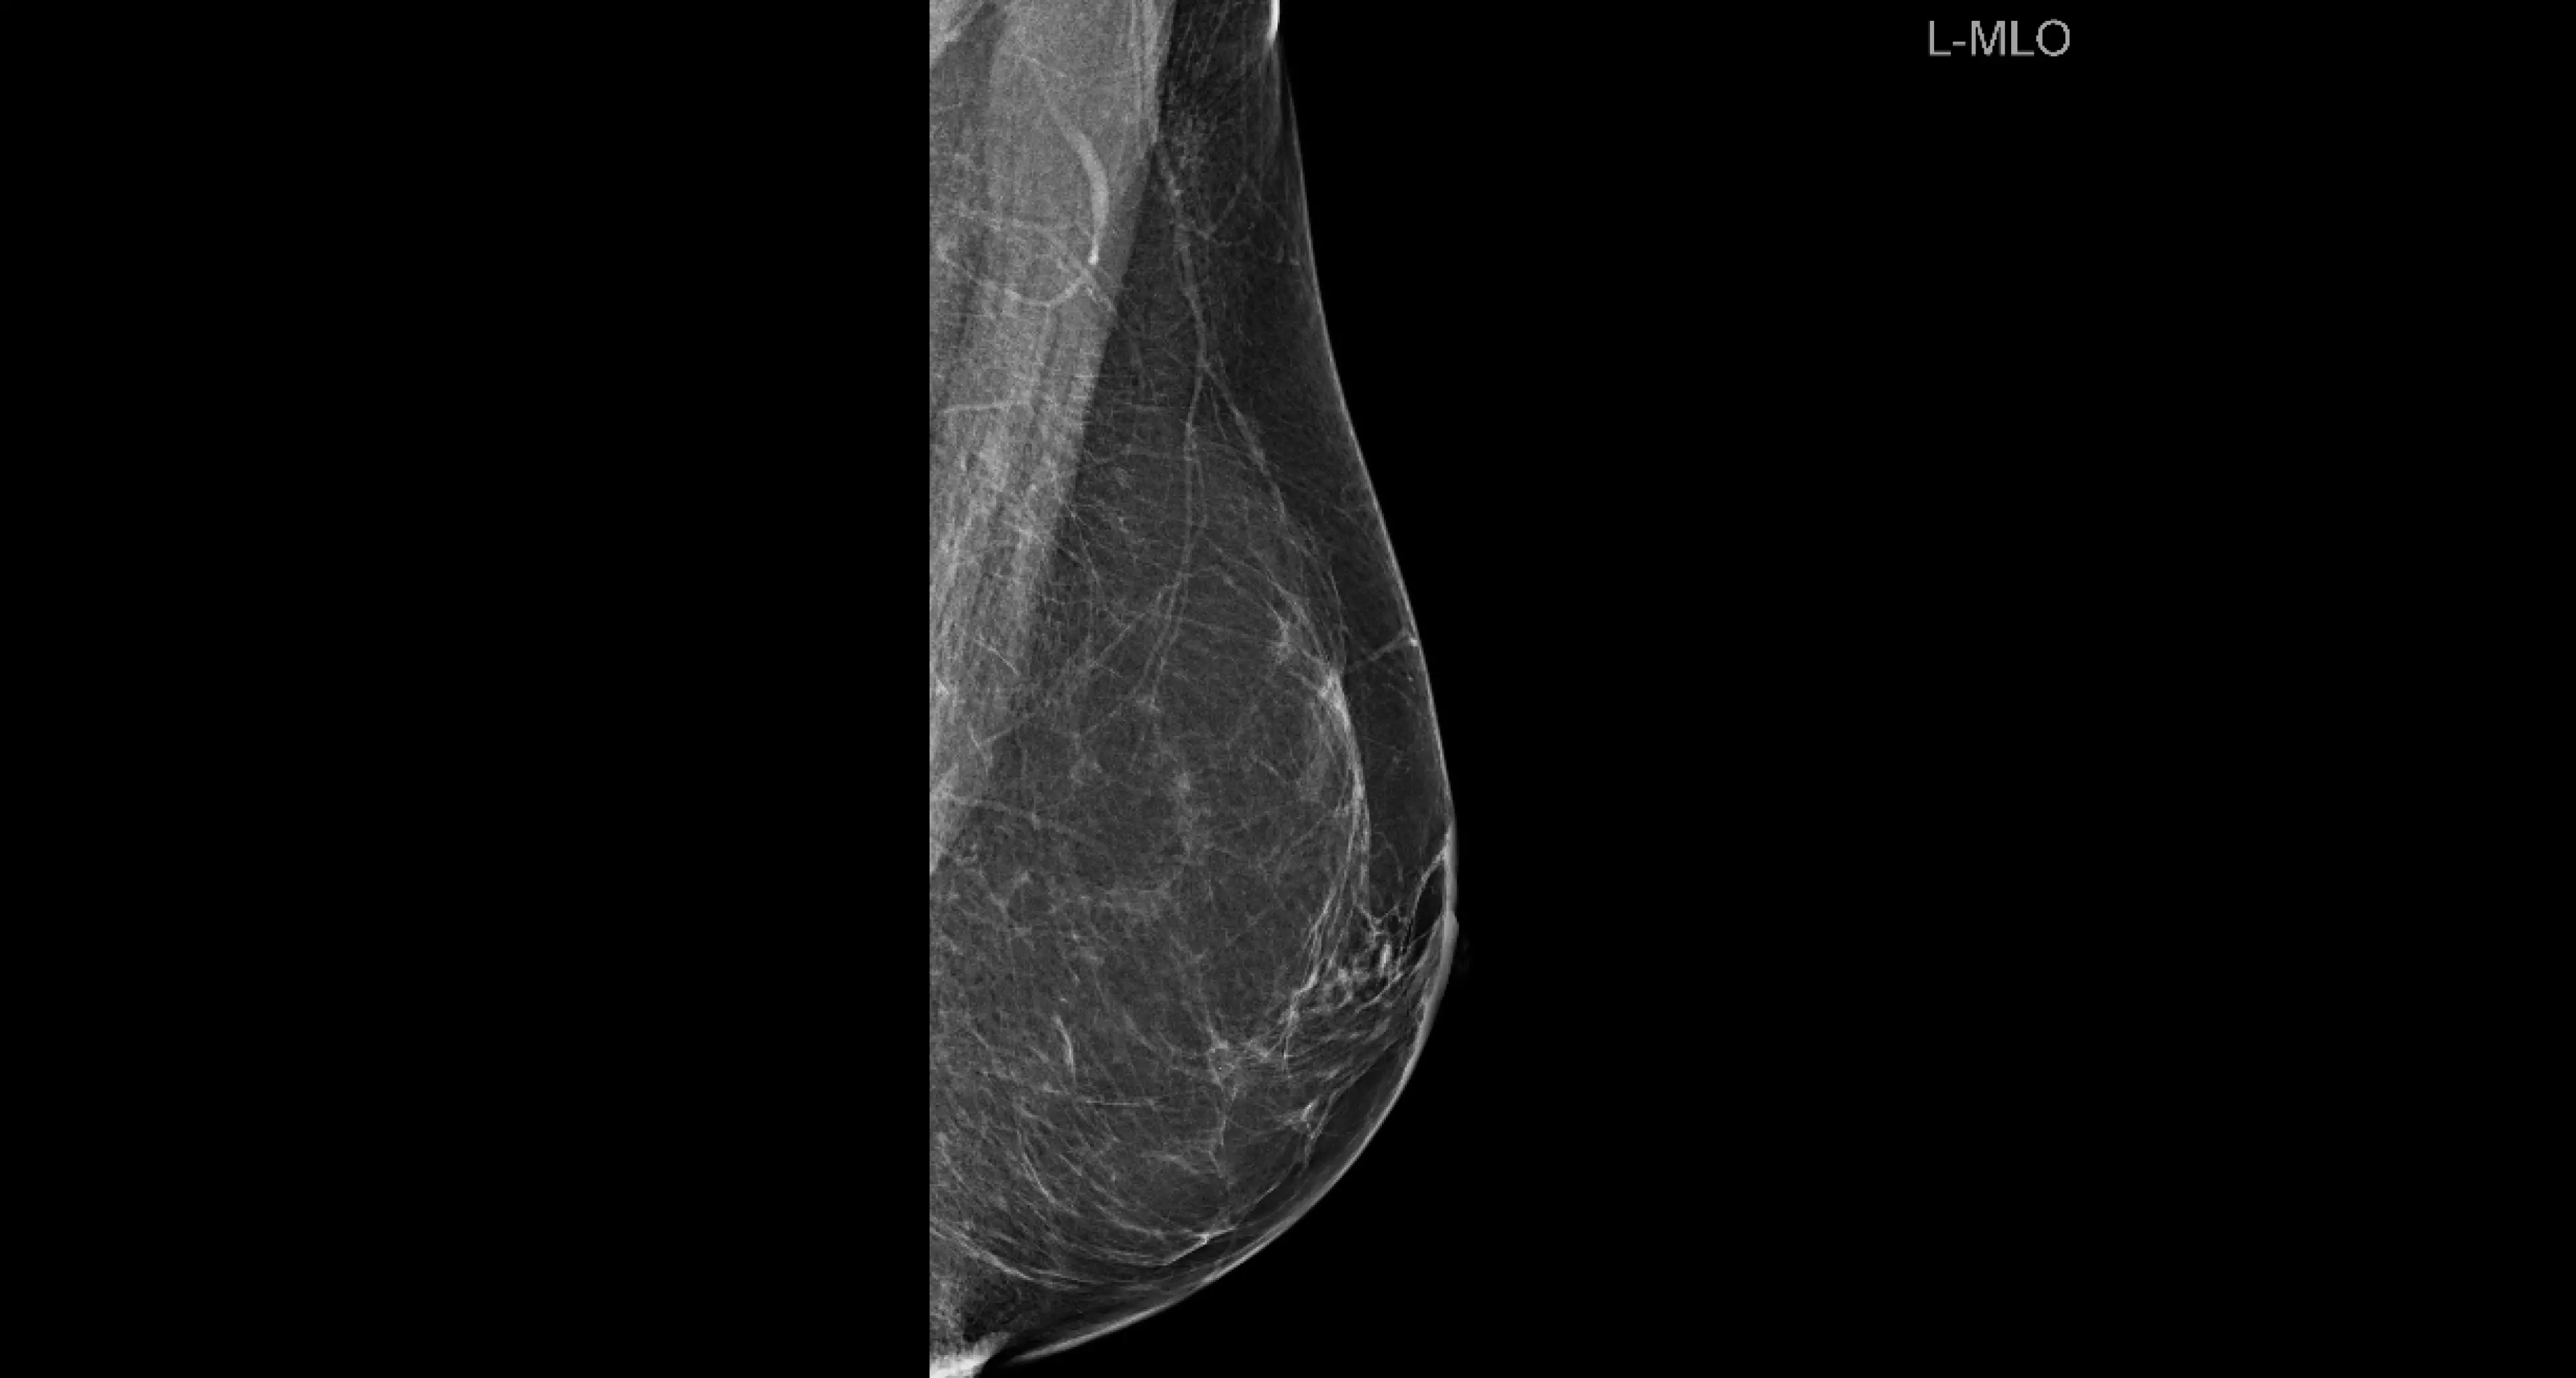

Prevencija podrazumijeva provođenje samopregleda dojki, periodičkih ultrazvučnih i mamografskih pregleda. Važno je i odazvati se na organizirani nacionalni probir za rano otkrivanje raka dojke 'MAMMA' koji uključuje žene u dobi od 50 do 69 godina.

- Samopregled dojki preporučuje se nakon dvadesete godine života, a trebalo bi ga obavljati jednom mjesečno, dok je s ultrazvukom dojke najbolje početi od 25. do 30. godine života kod žena s prosječnim rizikom za razvoja karcinoma dojke, ali i ranije kod žena s povišenim rizikom za karcinom dojke. Do četrdesete godine života dovoljan je klinički i ultrazvučni pregled jednom godišnje ako su klinički i ultrazvučni nalazi uredni. Nakon četrdesete godine preporučuje se mamografija svake dvije godine, ultrazvuk jednom godišnje, uz redoviti samopregled jednom mjesečno te uredne kliničke, ultrazvučne i mamografske nalaze - pojašnjavaju iz poliklinike Affidea Vita.

- Prva mamografija, kao i mamografske kontrole se preporučuju prema individualno procijenjenom riziku žene za karcinom dojke, ali najčešće se preporučuje s navršenih 40 godina života. Mamografija se u tom slučaju radi svake dvije godine, a između toga ultrazvučni pregledi. Iznimno, kod određenog sastava dojki, moguće je protokol pregleda mijenjati jer kod nekih se dojki promjene bolje vide ultrazvukom, a kod nekih mamografijom - napominju iz poliklinike Affidea Vita.